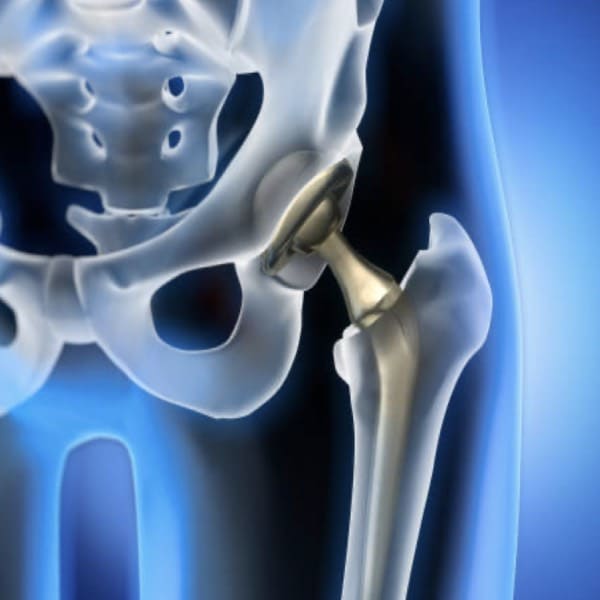

COXARTROSIS

Manejo especializado de Coxartrosis o artrosis de cadera.